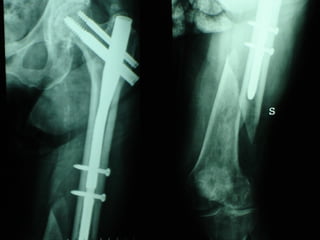

Dal Gennaio 2000 al Dicembre 2005 27 placche LISS di femore

INDICAZIONI COMUNI Fratture sovracondiloidee Fratture intercondiliodee Fratture diafisarie distali PARTICOLARI Fratture con grave osteoporosi Fratture periprotesiche

VANTAGGI CHIRURGIA MININVASIVA Mini Open Inserimento della placca sottocutaneo per scivolamento Viti percutanee Preservazione dei tessuti molli Ridotto danno vascolare Rapida ripresa funzionale

F, 68 y

LISS  NCB

NCB